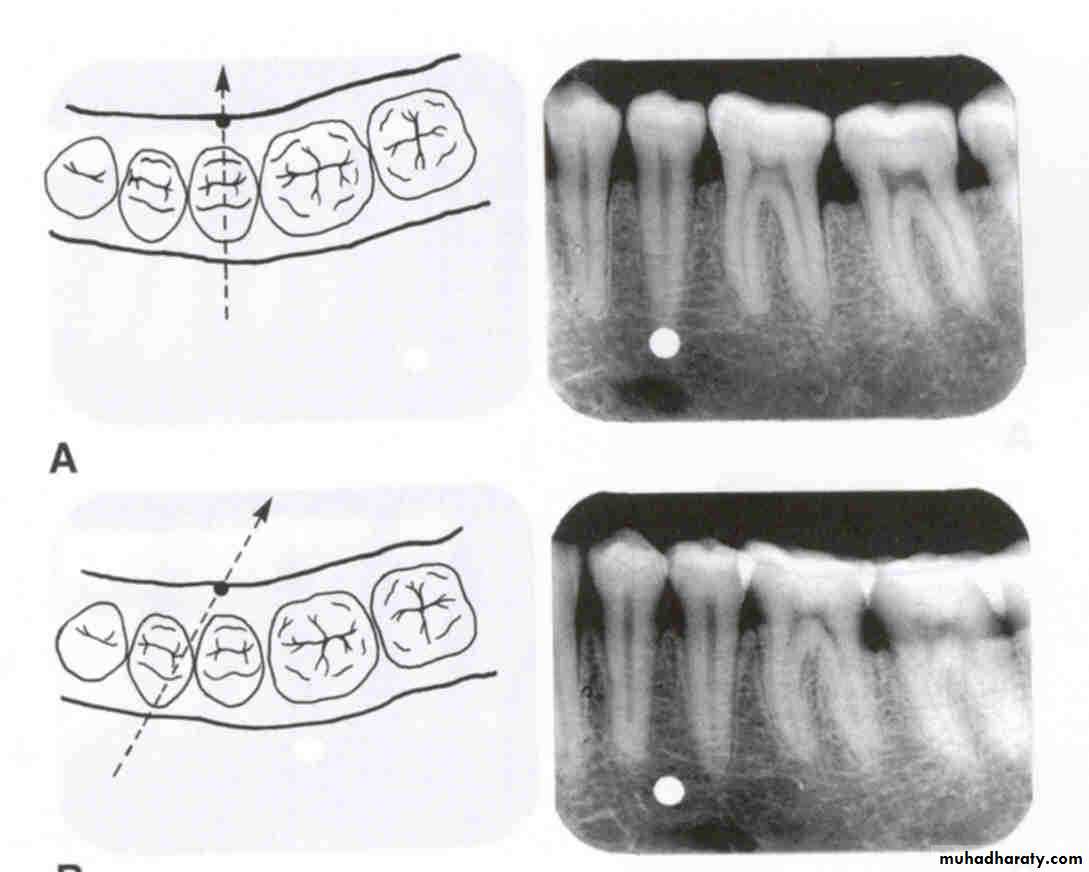

Relative positions of radiographic images of two separate objects changes ,when projection angle at which images were made, is changed.

The image of Tooth that is farther away from X-ray tube(lingual) moves in same direction as tube and Image of Tooth closer to X-ray tube (Buccal) moves in opposite direction.

SLOB

Same Lingual Opposite Buccal

Lingual body moves in same direction

Buccal body moves in opposite direction

SLOBFor the SLOB rule to work, there must be a change in the horizontal or vertical angulation of the x-ray beam as the tube head is moved. This change in angulation will alter the relationship between the object of interest and the reference object, allowing you to determine the buccal or lingual location.

Horizontal movement

In the diagram at left, the tube head is moved distally and the beam is directed mesially. On the radiograph, the buccal object of interest (yellow) moves mesially (opposite to tube head movement) in relation to the second molar and the lingual object of interest (red) moves distally (same direction as tube head) in relation to the second molar.

distalHorizontal movement

In the diagram at right, the tube head is moved mesially and the beam is directed distally. On the radiograph, the buccal object of interest (yellow) moves distally (opposite to tube head movement) in relation to the second molar and the lingual object of interest (red) moves mesially (same direction as tube head) in relation to the second molar.